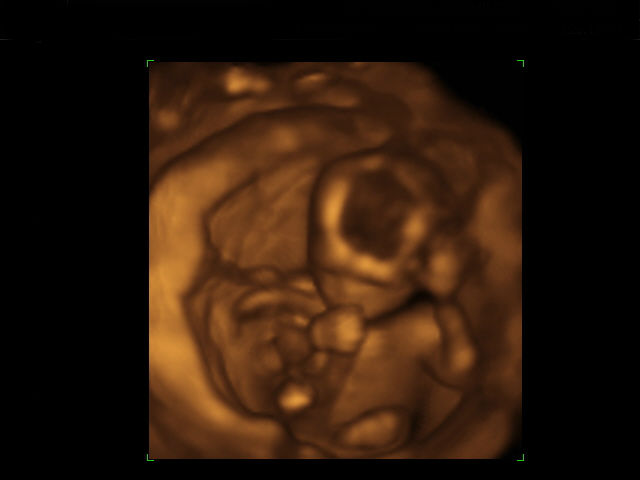

Любой, кто общался с детьми, наверняка замечал, что они тянут в рот практически всё, что окажется у них под рукой. То же самое происходит и с эмбрионами: даже при ультразвуковом сканировании заметно, что ещё нерождённый малыш почти всегда держит пальцы во рту и посасывает их.